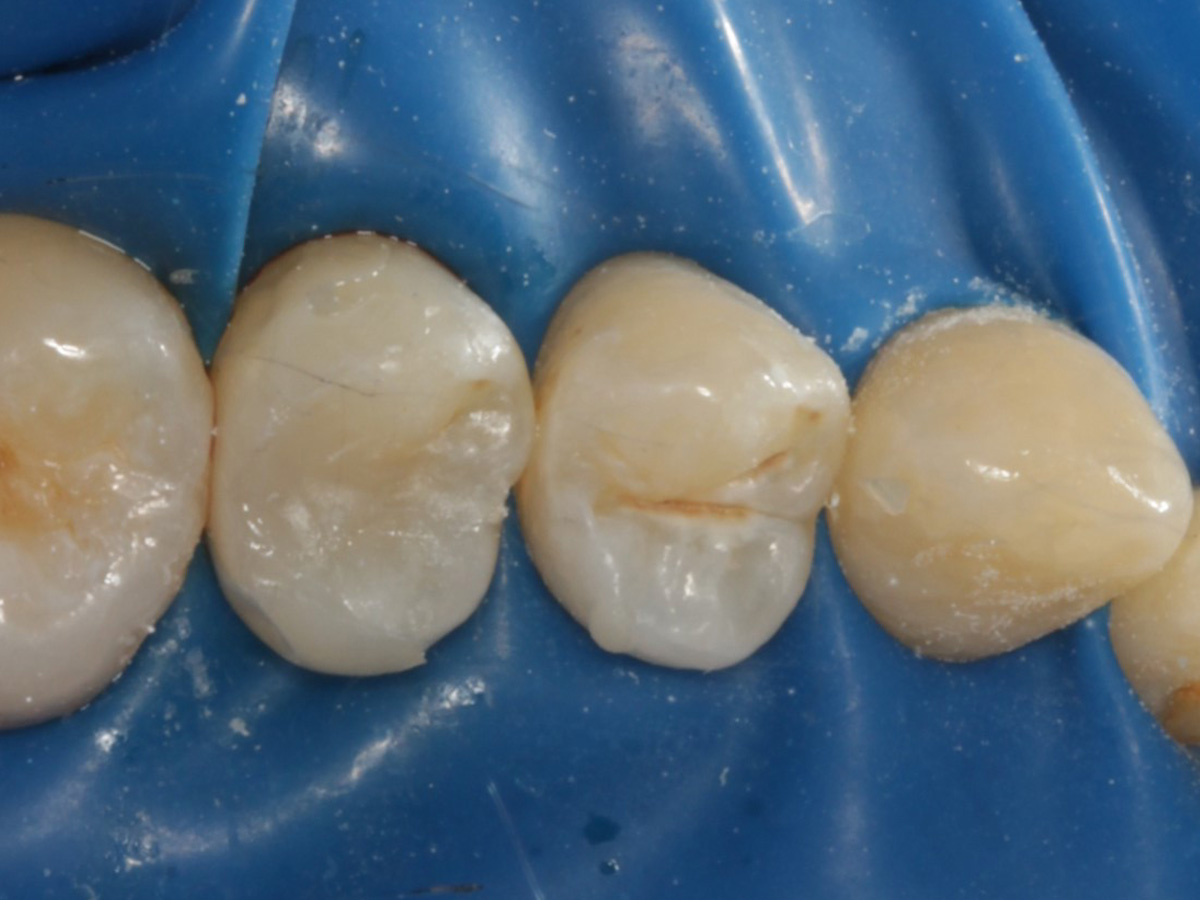

Abbildung 18

Fertige Restauration

Abbildung 19

Röntgenkontrolle: approximal fast auf Knochenniveau endender spaltfreier Füllungsrand dank interproximaler tieferer Verlängerung der Evolve Matrize